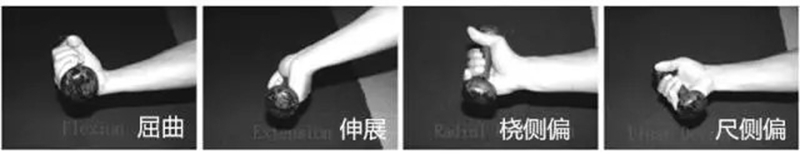

2.功能检查

屈曲(Flexion):0°~90°

伸展(Extension):0°~70°

桡侧偏移(Radial Deviation):0°~15°

尺侧偏移(Ulnar Deviation):0°~45°